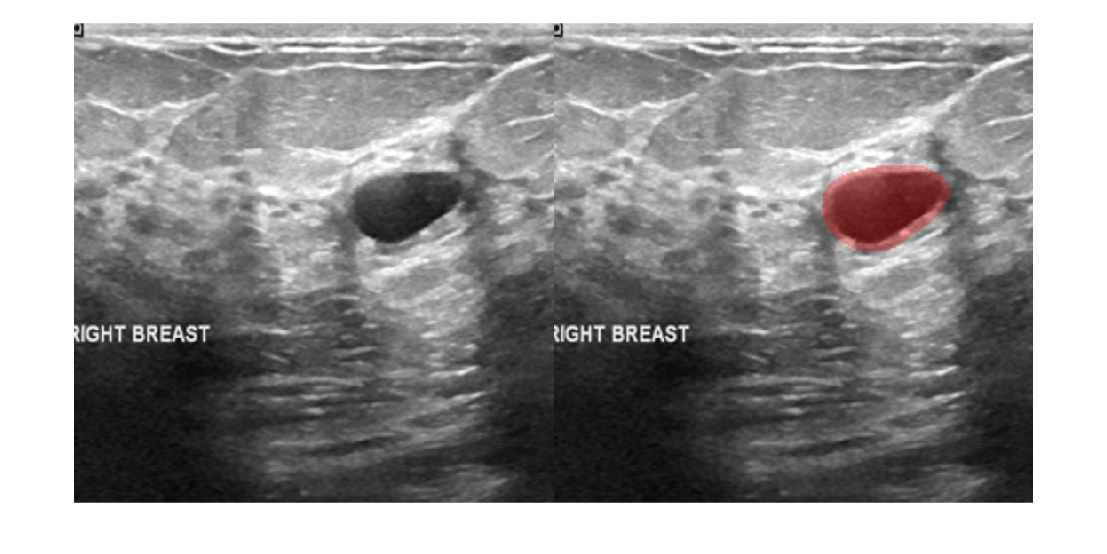

Perform interactive medical image segmentation using Medical Segment Anything Model (MedSAM) and deep learning. (Since R2024b) - Get Started with MedSAM in Medical Image Labeler

This example shows how to interactively segment objects in medical images and in cross-sections of medical volumes using the MedSAM algorithm in the Medical Image Labeler app. (Since R2025a)